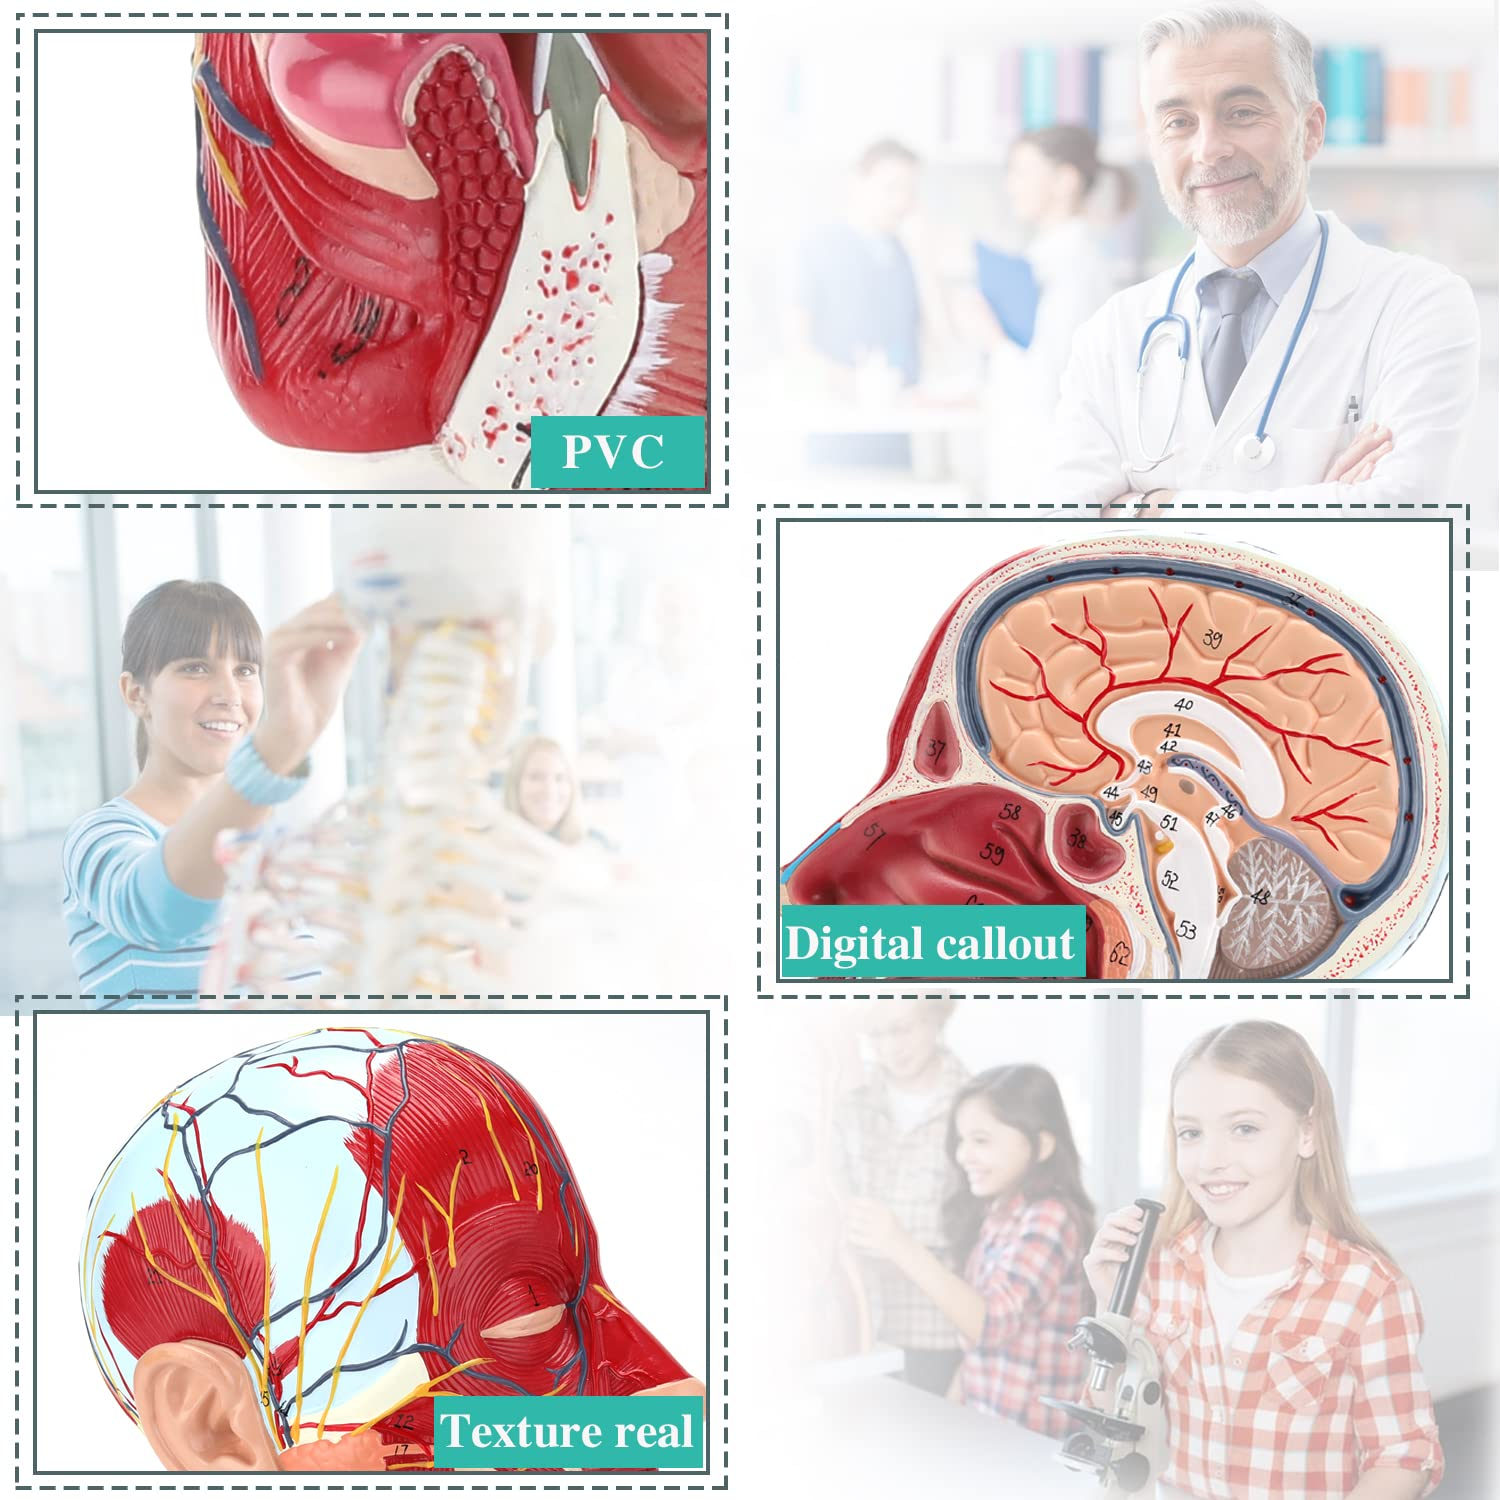

| Bahan | PVC |

【Model anatomi otak yang berkualiti tinggi, diperbuat daripada bahan PVC yang mesra alam, mudah dibersihkan. Model anatomi dicat tangan dan dipasang dengan perhatian yang paling terperinci.